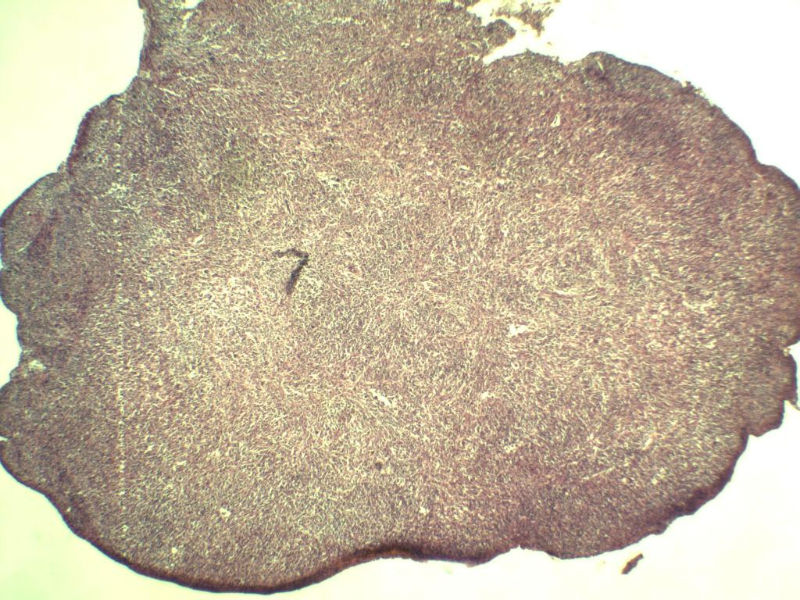

男,38岁,腹股沟 多枚淋巴结活检  直径 0.2-0.5 请各位老师看看 是什么 谢谢了!

"畏寒,发热咳嗽1年,加重伴腹部疼痛2月" 2月前患者感腹部疼痛不适伴大便呈稀大便,量不详,伴腰骶部疼痛,胸片:纵膈及右肺门多发性淋巴结肿大,进一步完善胸部CT:右肺及中叶病变,纵膈及肺门多发淋巴结肿大,结核性可能,脾脏增大,PPD(-),1个月来患者出现中上腹食欲不振,体重进行性消瘦,全身疲乏无力,3天前到医学院就诊,腹部B超:右肝囊肿,胆囊壁毛糙,脾大,胰周多个减弱回声,淋巴结不能除外,腹水,血常规示:WBC16.36x109 /L,N%14.25%,RBC2.63x1012/L ,HGB 66g/L 。右侧腋窝及腹股沟可扪及多枚淋巴结,压痛,无明显粘连。

腹股沟 多枚淋巴结活检图2

副皮质区增生,纤维化显著,细胞呈多形性,有一些多核巨细胞及一些异型细胞,病理性核分裂易见,胞浆红染,散在的小淋巴细胞,T细胞淋巴瘤不能除外,树突细胞肉瘤等鉴别。免疫标记。CD21、CD3、CD5、CD10、CD20、CD79a、PD1、CD68、CXCL13、KI-67、CD68、CD163等,据切片选择。不知对否。

淋巴结正常结构破坏,可见大的异型细胞,上皮样或梭形,恶性肿瘤,依据病史,首先考虑淋巴造血系统疾病,大中小细胞混杂,大细胞多,形态多样,可见多核瘤细胞,除以上考虑外需鉴别间变大、组织细胞肉瘤、指状突/树突细胞肿瘤、HL等,还需排除肉瘤或癌转移,尽管病人年轻,加上ALK、CK、S-100、CD1a。